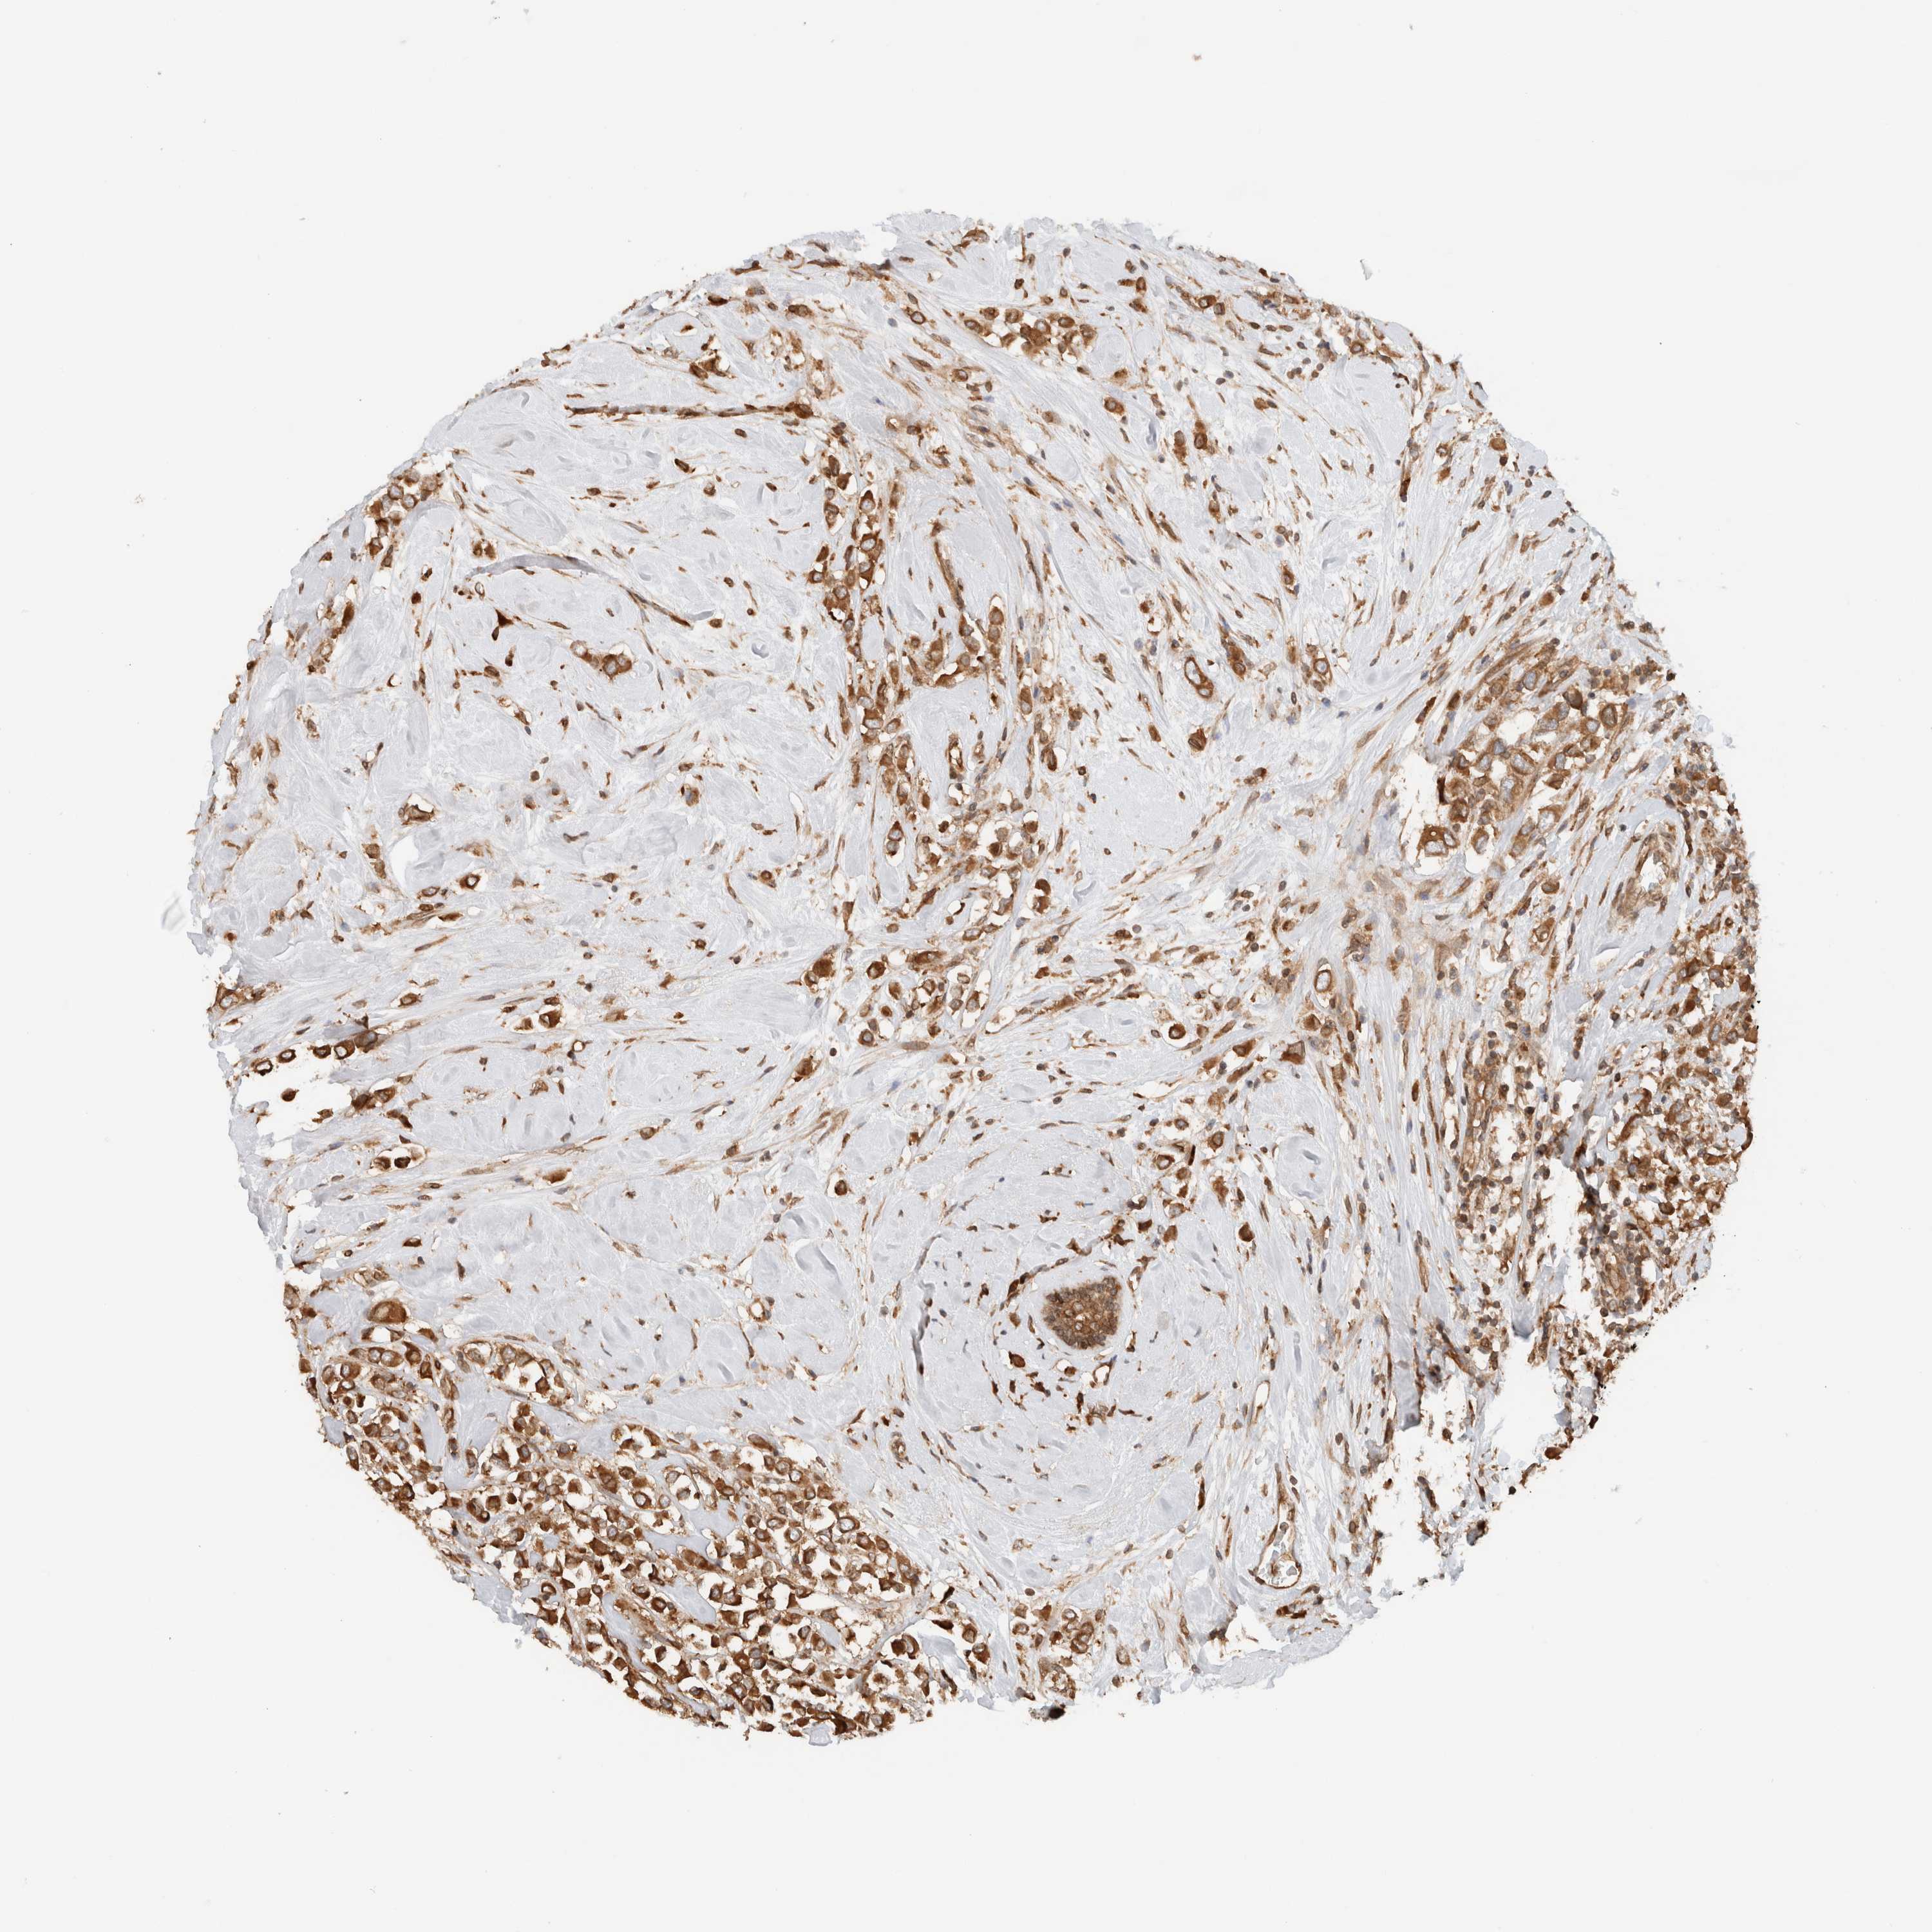

BRCA TCGA BRCA VALIDATION PROTEIN EXPRESSION